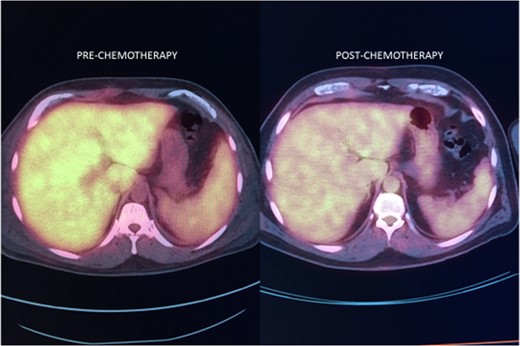

Noncutaneous IVLBCL in particular is normally associated with poor long-term prognosis. In most cases, IVLBCL is disseminated at the time of diagnosis, warranting treatment with systemic therapy [1]. Successful IVLBCL treatment has been achieved with modified R-VNCOP-B (etoposide, mitoxantrone, cyclophosphamide, vincristine, prednisolone and bleomycin plus rituximab) regimen [2]. R-CHOP therapy, utilized in combination with high-dose methotrexate therapy as prophylactic CNS coverage, has also been successful in other IVLBCL cases with hepatic involvement [3, 7].